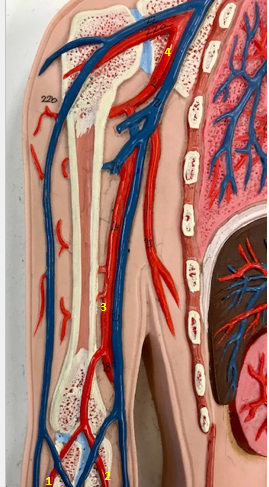

Tunica intima

Name the blue arrow

Lines lumen and release vasoactive chemicals

Function of tunica intima

Venous valves

Name the pink arrow

Prevent backflow of blood

Function of venous valves

Tunica media

Name green arrow

Vasoconstriction and vasodilation

Function of tunica media

Tunica externa

Name the purple arrow

Anchor and bind vessel

Function of tunica externa